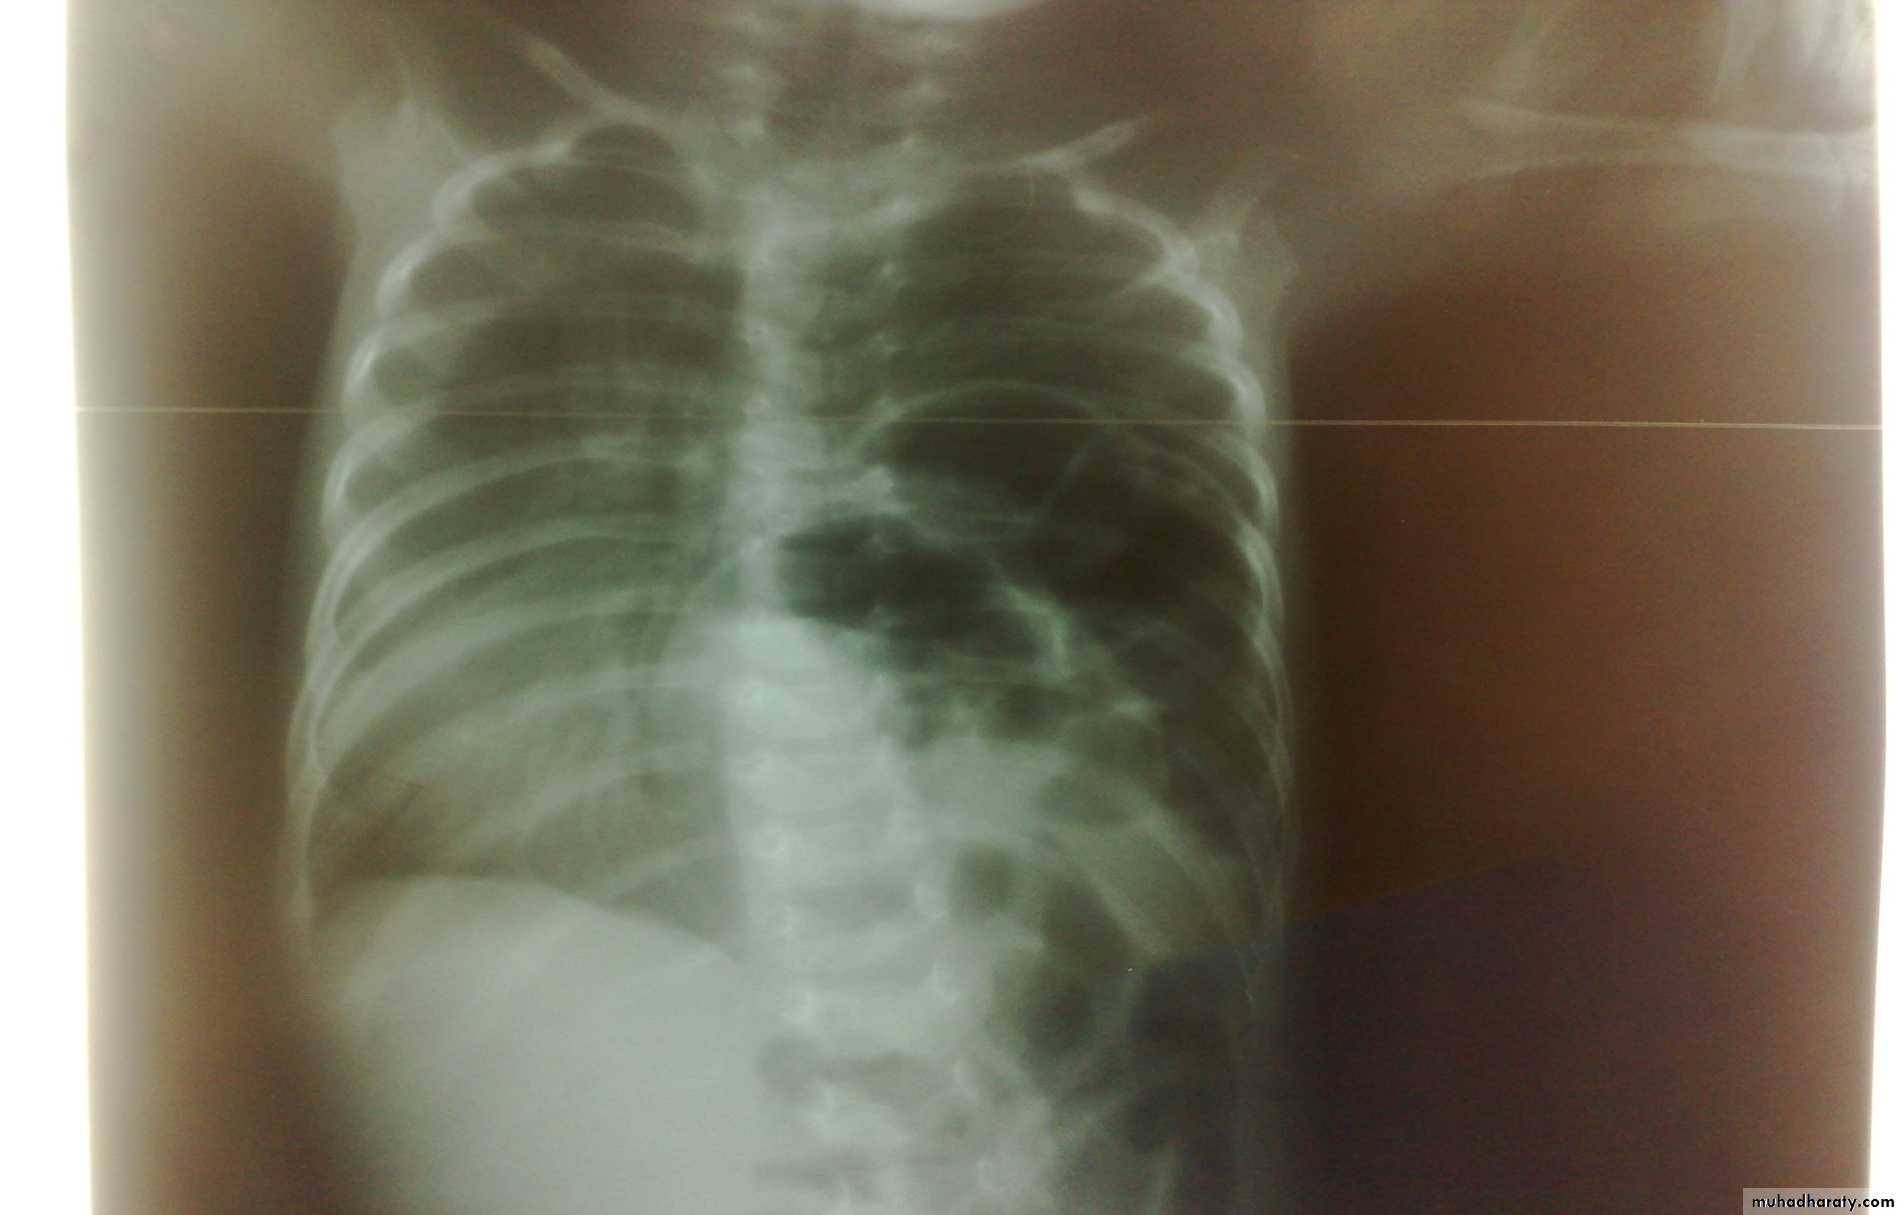

Respiratory Distress in the Newborn

Bowel Obstruction